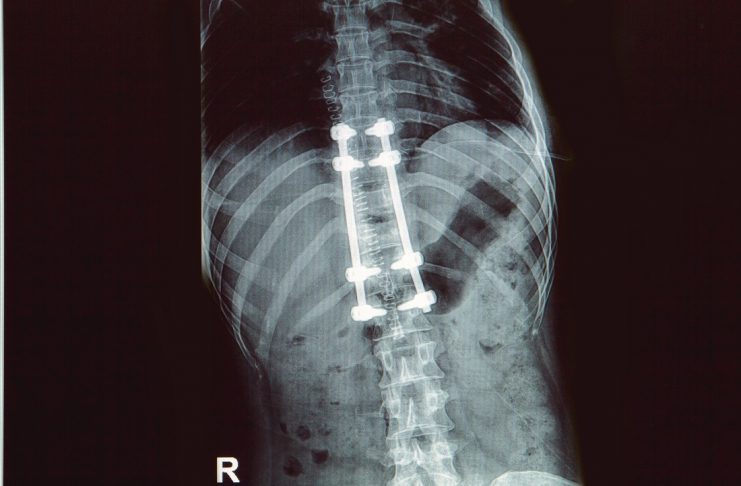

Known as epidural electrical stimulation, the new spinal cord implant allows for translation of neural messages from the brain to the spine. That in itself is rather unusual, as the physical nerves and spine are disconnected. Being able to bridge this gap is a massive breakthrough for the scientific industry as a whole.

What makes this implant most impressive is how it regenerates damaged nerve cells in the spine. That is why it allows one patient to take a few steps with the implant switched off. Long-term exposure to this technology will not necessarily heal the spinal cord as a whole. However, every little bit helps, and this technology seemingly checks a lot of the right boxes.